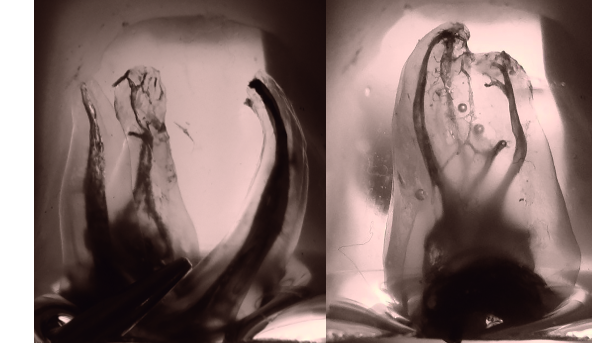

Successful endodontic treatment depends on a number of factors, including proper instrumentation, successful irrigation and decontamination of the root- canal system right to the apical terminus in addition to hard to reach areas such as isthmuses, and lateral and accessory canals[3,4] (Fig. 1a & 1b).